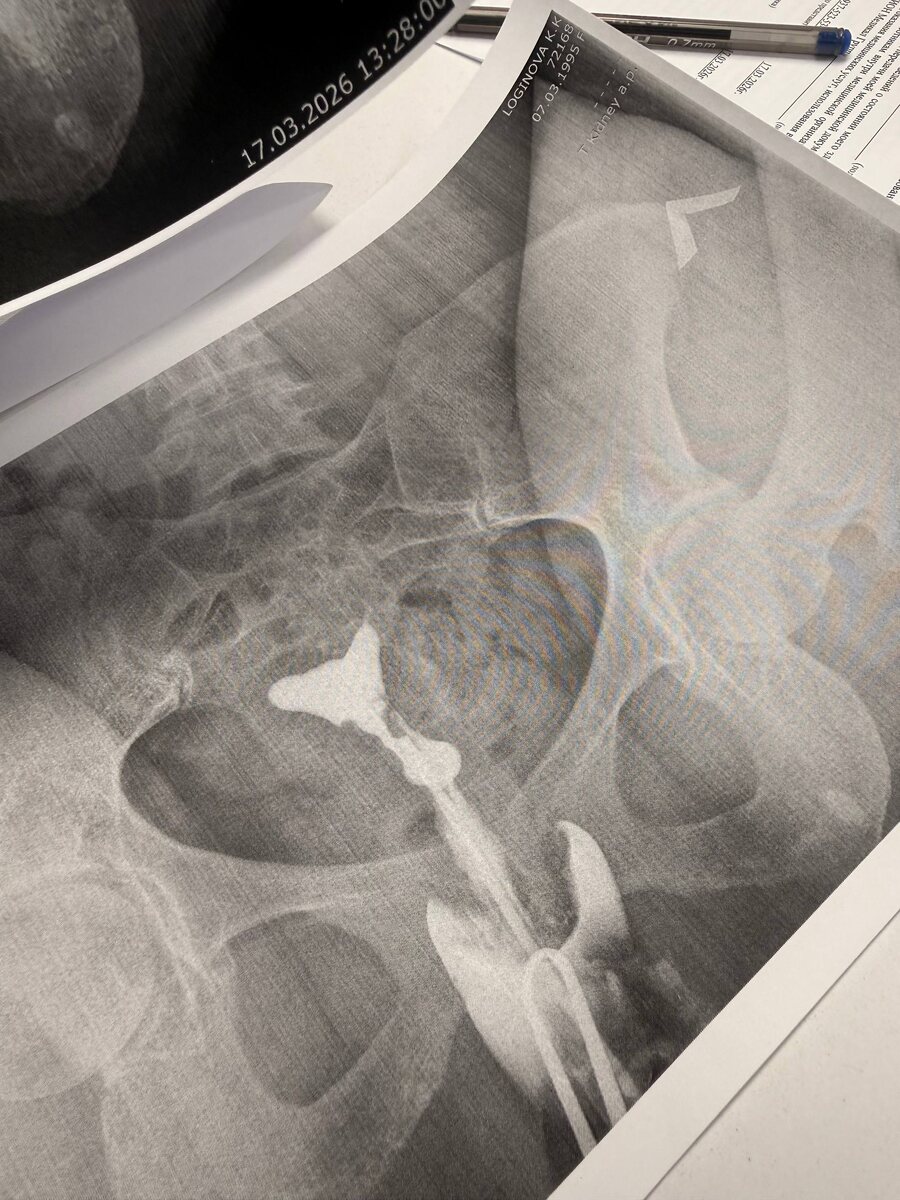

😞 Два исследования , двух разных пациенток ☝️ И два диагноза ☘️ 🎯У одной пациентки все хорошо- проходимые маточные трубы ✅ 🎯У другой - трубное бесплодие ! При том что одни роды 10 лет назад были , и беременость была самостоятельная. Не представляете как тяжело врачу говорить такие заключения и направлять на ЭКО 🥺

🎯У одной пациентки все хорошо- проходимые маточные трубы ✅

🎯У другой - трубное бесплодие ! При том что одни роды 10 лет назад были , и беременость была самостоятельная.

Не представляете как тяжело врачу говорить такие заключения и направлять на ЭКО 🥺